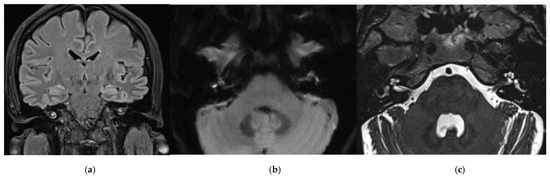

3.1. CASE 1

3.2. CASE 2